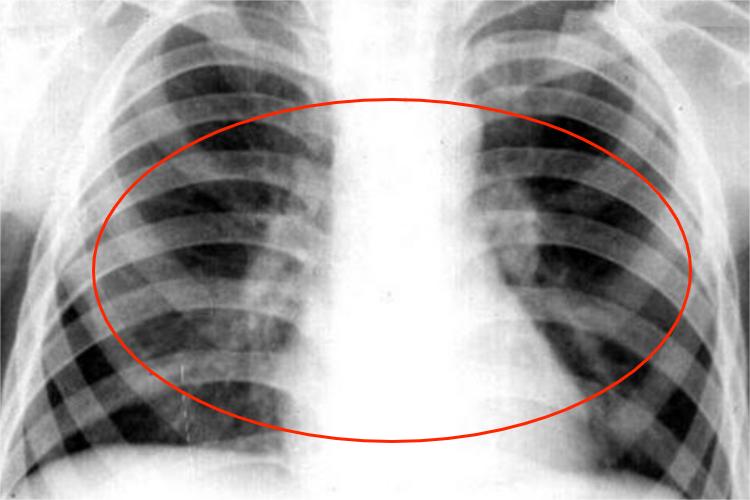

肺结核哑铃状阴影是指X线检查中可见肺内原发病灶和肺门淋巴结阴影,两者间有结核性淋巴管炎的条索状阴影相连,形成哑铃状阴影。患者可有长期低热,伴有倦怠、乏力感、夜间盗汗,以及咳嗽、咳痰、咯血等,部分患者有固定性针刺样胸痛。